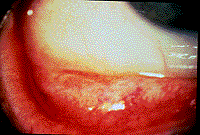

As is true of many contact lens related problems, allergic conjunctivitis is most effectively treated with lens discontinuation (figure 6). Patient symptoms are ameliorated with cool compresses, ocular irrigation, and topical antihistamines / decongestants. Rarely, topical steroids are warranted. Topical non-steroidal anti-inflammatory agents can benefit the allergic conjunctivitis patient by virtue of their prostaglandin inhibition. However, as they exert their therapeutic influence on the cyclo-oxygenase pathway they do not influence leukotriene synthesis. In more severe allergic presentations topical steroids are acceptable, though this is rarely necessary. Oral therapeusis is often beneficial as an adjunct in more symptomatic cases of allergic conjunctivitis. In particular, Benadryl can assist with acute bulbar chemosis while agents such as Seldane, Hismanal, and Claritin are effective in chronic prophylaxis. It is important to review the patient's drug history before recommending OTC or prescription antihistamines. Drug interactions or allergic responses can compound the initial problem. The dosage should be titrated so as to maximize the therapeutic response with the least amount of medication. Generally, allergic conjunctivitis patients experience significant improvement within 72 hours of initiating treatment.